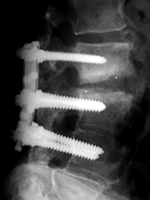

| Pedicle fixation screws and rods |

| 20 year-old woman with L1 vertebral body compression fracture treated with T12-L2 posterior spinal fusion using pedicle screws at T12 and L2 with connecting rods on each side. |